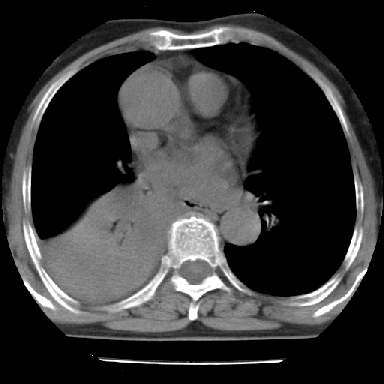

以下是引用苯小孩在2007-4-13 16:20:00的发言:[br]1、右下肺中央型肺癌并阻塞性肺不张、肺内转移、胸椎右侧附件亦有转移<横断层面第8层>.[br]2、右侧胸腔积液.

以下是引用swyyy2007在2007-4-13 15:31:00的发言:[br]右肺门下区肿块,右肺下叶支气管阻塞,右肺下叶不张,右侧大量胸腔积液,右肺中叶见结节状高密度影,边缘清,纵隔内见肿大淋巴结。首先考虑右下肺中心型肺癌伴右肺下叶不张、中叶、纵隔淋巴结转移。右侧胸腔积液。